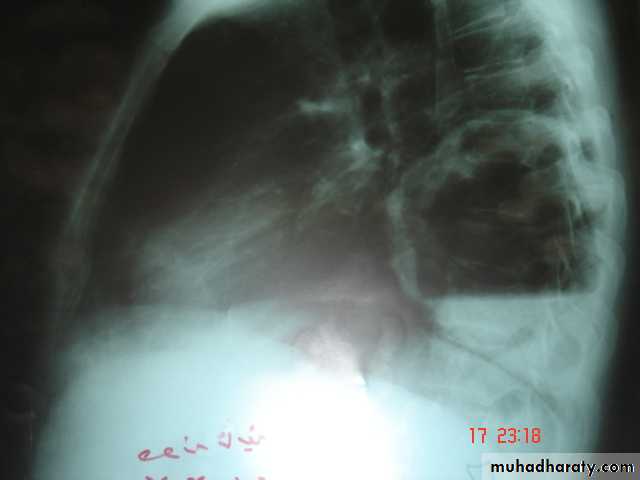

• Radiological Findings

• 1-Smooth homogenous opacity (Intact H.C).• 2-Partial rupture (peri-vesicular pneumocyst).

• 3-Complete rupture (Water –lilly sign) .

• 4-Formation of lung abscess(Air –fluid level) .